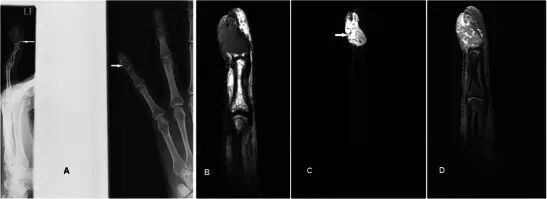

图11.神经纤维瘤的53岁男性,4 - 5年时间的左手拇指甲床无痛肿胀。 患者没有神经纤维瘤病或任何其他临床表现的个人或家族史,并且这可能是孤立的病变。 (a)T1w序列显示在拇指尖端处的分叶皮下损伤,与包括皮肤的肌肉等高,在下方远指骨上具有轻度压力侵蚀(箭头)。 (b)结节在T2w-FS序列上是非均质的高信号。 (c)看到相当均匀的增强

图14.血管球瘤在一个30岁的女性,在左无名指的尖端疼痛的肿块。 (a)平片显示沿着左手无名指远端指骨的尺骨方向(箭头)的明确边界的扇形缺损。 (b)T1w序列显示平滑的,良好外切的皮下损伤导致中间信号的手指的尖端的骨压力侵蚀。 (c)T2w-FS序列显示病变是极度和均匀的高信号。 (d)看到强烈和均匀的增强

恶性骨病变Malignant bony lesions 骨转移到手(acrometastases)是罕见的。 恶性肿瘤的最常见的原发部位是肺,肾和乳腺,并且它们通常表示不良预后[49]。显示出膨胀性破坏性溶骨性破坏X线平片通常是在适当的情况下可以下(图18)诊断。如果对临床病史或异常放射照相外观有任何不确定性,MR可能是有用的(图18b-d)。治疗是姑息治疗,但可以提高生活质量。

图18.一个67岁男性的肺腺癌病史的骨转移,在右侧背部的内侧方面呈现2周的肿胀和疼痛病史。 (a)平片显示第五掌骨的透性破坏(箭头)。 (b)T1w序列显示具有浸润性软组织,主要是异质中间信号的第五掌骨的破坏。 (c)病灶在T2w-FS序列上是非均质的高信号。 (d)看到延伸到相邻软组织的非均匀增强

软骨肉瘤是成人中最常见的原发性骨恶性肿瘤,并且可以作为良性软骨瘤损伤(例如软骨瘤)的恶性变性发生。 平片显示典型的“环 - 弧”矩阵,其具有内皮层扇形和皮层变薄,但是在更高级别的亚型中,经常存在骨折破坏和不规则边缘[50](图19a)。 MR通常用于局部分期(图19b-d)。 对远端指骨的病变的鉴别诊断是血管球瘤,但是显示主要可扩展的骨病变的平片显示有效地排除了它。

图19.低级软骨肉瘤在一个47岁的女性,呈现一个缓慢扩大的企业肿胀左侧小指的远指骨几个月与指甲畸形。 (a)平片显示在小指的远指节中的可扩张的裂解性骨病变,具有标记的内皮层破裂和随着背侧皮层的破坏而变薄。 环 - 弧密度暗示着软骨形成基质(箭头)。 (b)T1w序列显示在中指的小指远端指节中的可扩展的骨病变,软组织成分破坏并穿透背皮质以涉及皮肤和指甲。 (c)在具有低信号区域(箭头)的T2w-FS序列上,病变是非常高的信号,典型的软骨形成基质。 (d)后对比度有异质增强